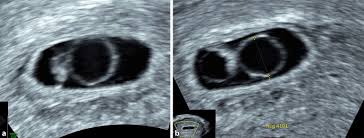

Der Dottersack Ein Wichtiger Marker Beim Ultraschall In Der Fruhschwangerschaft Springerlink